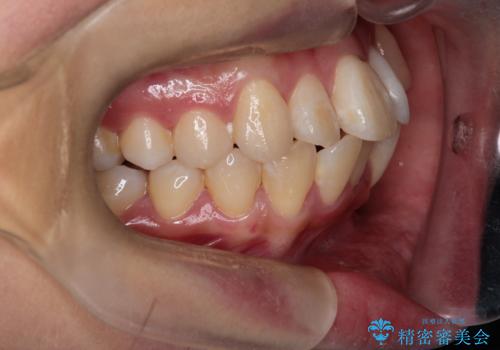

八重歯: 突出していた八重歯を歯列内に誘導し、デコボコを解消しました。

正中のズレ: 歯を左右対称に移動させることで、上下の歯の中心線を正確に合わせ、顔全体のバランスも改善しました。

治療の結果、長年気にされていた八重歯と正中のズレが解消し、機能的にも整った理想的な歯並びを獲得。目立たない装置で治療を完遂し、自信を持って笑える美しい笑顔を手に入れていただけました。